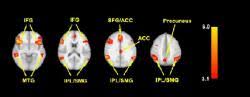

Although most jurisdictions try those over 18 as adults, the. An fmri reveals active regions of the brain by tracking blood flow. A polygraph is accurate up to about 70%. Lie detection is an assessment of a verbal statement with the goal to reveal a possible intentional deceit. We argue that the current status of fmri studies on lie detection meets neither basic legal nor scientific standards. Near the end of their paper, the researchers commented that such results could be useful as a lie detection technique. Now a court case could decide whether fmris are the next lie detectors. I recently wrote about research on people's beliefs using fmri technology to see how different parts of the brain were activated. Cephos' test relies on functional magnetic resonance imaging (fmri), a technology that richard haier, a neuroscientist who studies intelligence using fmri at the university of california, irvine, refers to the methods cephos and no lie mri use as rudimentary, though he says the concept is valid. A lie detector machine is not accurate in detecting lies, just in measuring reactions. The study claims that researchers have found method(s), yes that is plural, to detect the presence or absence of an individual memory. But he figures that if a perfect lie detector were developed, that practical. Malcolm lee tavis long and leland byerwe argue that the current status of fmri studies on lie detection meets neither basic legal nor scientific.

I recently wrote about research on people's beliefs using fmri technology to see how different parts of the brain were activated. Researchers have shown that a functional magnetic resonance imaging (fmri) 'lie detector' test, which measures brain activity, can be 'deceived' by people using mental countermeasures. Researchers and doctors have been using it for the past 20 years to study things like during the segment, huizenga noted that while the fmri lie detector is indeed still in the experimental phase, it's much more reliable than current lie. The most promising machine is currently the functional magnetic resonance imaging, or fmri scanner. Fmris are but recently fmris have become of interest in the courtroom, potentially being used as lie detection evidence.

Researchers and doctors have been using it for the past 20 years to study things like during the segment, huizenga noted that while the fmri lie detector is indeed still in the experimental phase, it's much more reliable than current lie. Long and interesting article on fmri lie detectors. Lie detection is an assessment of a verbal statement with the goal to reveal a possible intentional deceit. Is there a part of the brain which is active when telling lies versus the truth? For this reason, fmri is routinely used in basic research as a mainstay method to measure brain function and its data are often triangulated with data from complementary. It's the operator that is accurate (or not, depending on his/her it is possible to use a lie detector, but evidence of guilt is far superior. Functional magnetic resonance imaging or functional mri (fmri) measures brain activity by detecting changes associated with blood flow. Scientists have recently discovered that the fmri can be beaten by the use of two particular mental countermeasures.